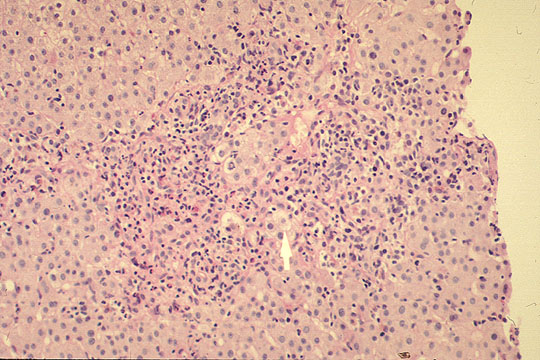

Portal and periportal inflammation

Fig 89 - PORTAL AND PERIPORTAL INFLAMMATION: Presence of both lobular and portal inflammation. This illustration shows marked protal and periportal inflammation with some hepatocellular ballooning degeneration.